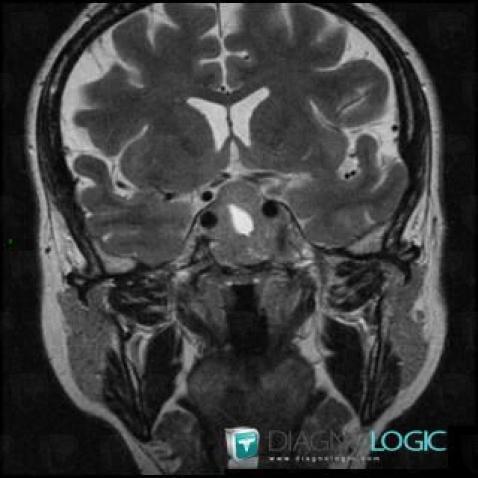

Macroadénome hypophysaire, Hypophyse et région parasellaire, IRM

Voici les informations spécifiques à l'image clé ci dessus:

- Diagnostic Macroadénome hypophysaire, Localisation(s) Hypophyse et région parasellaire, comportant les gammes Lésion en hypersignal T2 sellaire ou parasellaire